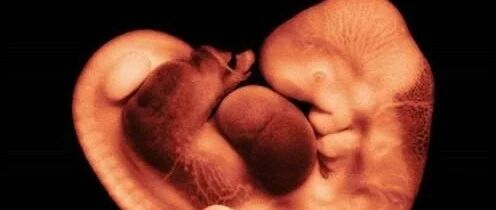

改善男性精子质量的一些方法

来源:付虹大夫

时间:2020-10-25